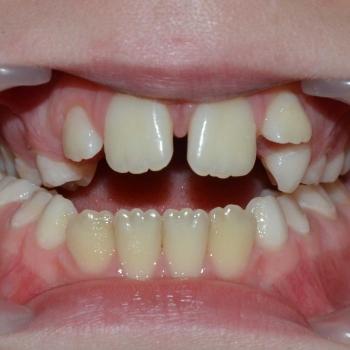

Csenge és édesanyja még vegyesfogazati időszakban, az egyetemen kerestek fel többszörös funkciós és esztétikai problémák miatt. Az első vizsgálat alkalmával súlyos nyitottharapást, keresztharapást, középvonal eltolódást, Angle II. osztályú eltérést, nyelvlökéses nyelést, helyhiányt diagnosztizáltunk, illetve elképesztő ritkaságként felcserélődött szemfog-kisőrlő csírákat találtunk a jobb oldalon.